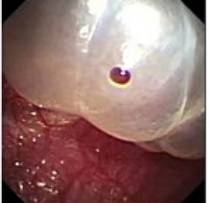

近年来,贵州航天医院各科室紧跟医学前沿,不断强技术、补短板,大力开展新技术、新项目,完成了许多高精尖、高难度、本地区“首例”的技术,填补了医院医疗技术空白,满足了群众日益增长的医疗需求。 贵州航天医院呼吸与危重症医学科是贵州省内呼吸疾病治疗规模最大,诊疗项目最全的呼吸疾病品牌科室,呼吸介入技术达到了全国先进水平,在贵州省内处于领先的地位。 本期,我们将为大家带来呼吸与危重症医学科特色技术——内科胸腔镜技术诊断和治疗胸腔疾病。 案例分享 患者苟某某,因劳累、气促,不明原因胸腔积液在某县一医院采取反复抽水等治疗手段效果不佳,当地医院考虑到患者年龄大(77岁),基础疾病较多,病情复杂,结合当地诊疗水平能力情况,建议转到上一级医院诊治,通过我院与该院建立的呼吸专科联盟绿色通道转入了我院。 患者入院后,呼吸与危重症医学科第一时间复查胸部CT,提示:右肺中叶、左肺感染,纤维化灶,左侧中量胸腔积液,右后侧胸膜轻度增厚,心包少量积液;并完善心电图、血常规、凝血功能、生化指标等术前检查。经科室专家团队集体讨论,得出患者左侧胸腔积液可能原因:结核?恶性?其他?冠心病、心功能不全、高血压病3级(高危组)、陈旧性肺结核复发?肺部感染;为进一步明确诊断,在充分评估、做好术前准备及应急预案、与患者及家属沟通的情况下,决定为患者进行内科胸腔镜检查术。 科室在患者入院第3天便实施了内科胸腔镜检查术,经检查取活检,病理不排除胸膜间皮瘤,送遵义医科大学附属医院病理会诊后诊断:胸膜间皮瘤。明确诊断后,科室专家团队为患者制定了个体化的治疗方案,患者病情很快得到有效控制,最终满意出院。半年后,医院通过电话回访,患者病情稳定,生活质量明显改善。 什么是内科胸腔镜 内科胸腔镜(medical thoracoscopy,MT)是一项微创诊断和治疗胸腔疾病的重要技术。主要应用于无创方法不能确诊的胸腔积液和胸膜疾病,通过局部麻醉后在胸壁做一个小切口,插入胸腔镜,直接观察胸膜、肺表面、纵隔等部位的病变情况,可进行活检、粘连松解及胸膜固定等操作。具有创伤小、恢复快、诊断准确性高等优点。 内科胸腔镜原理 内科胸腔镜是一项利用现代光学技术和成像技术的侵入性操作技术,应用电子支气管镜、硬质或软硬结合(半硬)的胸腔镜的一种电子内窥镜,末端装有连接着显示屏的微型摄像头。通过胸壁1-2cm左右的小切口,将内科胸腔镜及专用器械(戳卡套管)通过小切口进入胸腔,微型摄像头将胸腔内的情况投射到显示屏幕上,医生可以通过镜头全面、直观地观察患者胸腔内情况,了解胸膜病变确切位置和形态改变,还可对胸膜上的病变进行活检及治疗的操作技术,安全、微创、几乎无痛地“揭秘”不明原因的胸腔积液。 内科胸腔镜技术优势 (一)安全性高:仅需局部浸润麻醉,并发症发生率相对较低,对患者的身体条件要求较低。 (二)操作简便:操作时间短,痛苦少,患者耐受好。 (三)微创性:切口小,对患者身体损伤小,术后疼痛轻,恢复快。 (四)高分辨率成像:清晰显示胸腔内细微病变,提高诊断准确性。 (五)可直视操作:直接观察病变,进行精准活检和治疗。 (六)适用范围广:可用于不明原因胸腔积液、胸膜疾病、肺部疾病等的诊断和治疗。 (七)费用低:与外科胸腔镜比较费用低廉。 内科胸腔镜技术是贵州航天医院呼吸专科和呼吸介入诊疗优势的一部分,在2016年率先开展了内科胸腔镜技术,年手术量约100余例,已建立了快速、精准、规范、有效的一体化诊疗服务体系。目前呼吸与危重症医学科内科胸腔镜技术广泛应用于不明原因胸腔积液、气胸、脓胸的诊断和肺癌、弥漫性恶性胸膜间皮瘤等的分期,恶性或复发性胸腔积液、早期脓胸、自发性顽固性气胸的治疗。 镜下常见表现:单发或多发结节、灰白色弥漫性粟粒样结节、胸膜充血、水肿、胸膜增厚及纤维分隔或粘连带形成。 诊断方面: 胸腔积液的病因诊断。内科胸腔镜对恶性胸腔积液的诊断率可高达90%以上,胸腔镜对结核性病变诊断率极高,几乎达到96%以上。 腺 癌 恶性淋巴瘤 软骨肉瘤胸膜转移 滑膜肉瘤胸膜转移 结核性胸膜炎 治疗方面: 脓胸 肺大泡 贵州航天医院 呼吸与危重症医学科学科带头人 廖江荣 国务院政府特殊津贴专家 二级教授 主任医师 贵州航天医院副院长 国家级学术任职: 第二届中国医药教育协会介入微创专业委员会呼吸分会副主任委员 中国抗癌协会肿瘤微创治疗专业委员会常务委员 中国防痨协会结核病转化医学专业分会常务委员 第一届中国人体健康科技促进会呼吸介入专委会常务委员 中国医疗保健国际交流促进会结核病学分会第三届委员会常务委员 中国抗癌协会肿瘤微创治疗专业委员会粒子治疗学组第四届委员会委员 中华医学会结核临床专业委员会内镜介入委员 中华医学会放射学分会第十五届委员会介入学组呼吸系统介入专业委员会委员 北京健康促进会中青年专家委员会胸部疾病精准活检分委会副主任委员 中国医师协会介入医师分会第二届委员会肿瘤消融专业委员会委员 中国结核病防治综合质量控制专家指导委员会委员 亚洲冷冻治疗学会常务委员 世界内镜医师协会呼吸内镜协会常务理事 内镜临床诊疗质量评价专家委员会委员 “西部呼吸介入联盟”副理事长 专业擅长: 贵州航天医院 呼吸与危重症医学科简介 贵州航天医院呼吸与危重症医学科以呼吸危重症和介入呼吸病学为强力推手,以肺部感染性疾病及肺癌、肺小结节的早期精准诊疗、慢性呼吸疾病康复治疗为特色,以人才团队建设为核心的科室发展模式,现已成为省内呼吸疾病治疗规模最大,诊疗项目最全的呼吸疾病品牌科室。是贵州省医学重点学科、临床医学重点专科建设单位,遵义市首批呼吸重点学科、重点专科建设单位。是国家卫健委能力建设和继续教育肿瘤微创介入建设中心、贵州省县级医院微创介入培训中心、遵义市呼吸疾病临床医学中心。是国家呼吸医疗质量控制与管理哨点医院、遵义市呼吸内科专业医疗质量控制中心。是中国医药教育协会介入微创呼吸分会呼吸介入技术培训中心单位;国家卫健委海医会呼吸分会ROSE专委会“诊断性介入肺脏病学快速现场评价”培训基地;中国肺癌防治联盟“贵州航天医院肺结节诊治”分中心,中国人体健康科技促进会呼吸介入技术培训基地,贵州省中西医结合会呼吸学分会呼吸介入专委会主委单位。 基本情况 平均每年开展气管镜诊疗约4000例,经皮肺穿刺介入诊疗近千例,开展的项目包括经支气管镜(软、硬)下冷冻、氩气刀、高频电刀、球囊扩张、支架置入、超声内镜诊疗等气道介入诊疗技术,经皮肺穿刺活检及肿瘤消融术(微波、冷冻)、ROSE技术、内科胸腔镜诊疗及经血管介入诊疗技术,且多项呼吸介入诊疗技术在省内处于领先水平。 诊疗范围 航天医院呼吸专科擅长:致力于呼吸系统感染性、疑难性疾病的介入快速精准诊疗;肺癌与肺小结节早期精准诊疗水平项目提升。擅长于呼吸系统(肺)疑难病的诊断及危重病的救治,尤其在肺癌、肺小结节的早期诊断;肺癌综合靶向治疗;肺结核综合诊疗;肺部疾病的介入诊疗在省内处于前沿水平。 咨询热线 (一)呼吸与危重症医学科一病区 医生办公室:27677317 护士站:28614217 (二)呼吸与危重症医学科二病区 医生办公室:28691274 护士站:28690442 (三)呼吸与危重症医学科三病区 医生办公室:28692417 护士站:28690461 (四)呼吸与危重症医学科四病区 医生办公室:28616402、27677582 护士站:28614987、27677862